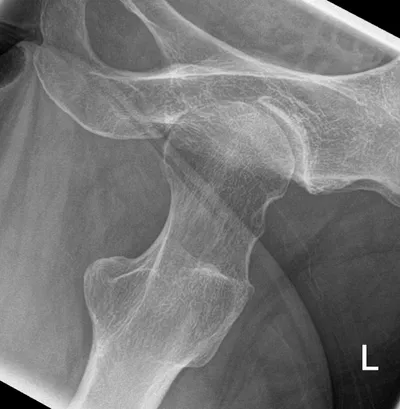

Osteoarthritis Radiology Images

Browse 3 medical images tagged with osteoarthritis. This collection includes various imaging modalities for medical education and reference.

- This collection contains 3 radiology images related to osteoarthritis, including various imaging modalities such as X-rays, MRIs, CT scans, and ultrasound images commonly used in medical diagnosis and education.